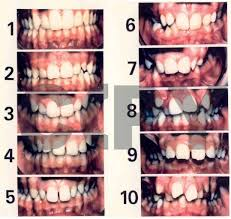

. Overbite

. Overbite

.Underbite

.Underbite

.Crossbite

.Crossbite

. Crowding

. Crowding

.Spacing / gaps

.Spacing / gaps

. Open bite

. Open bite

. Deep bite

. Deep bite